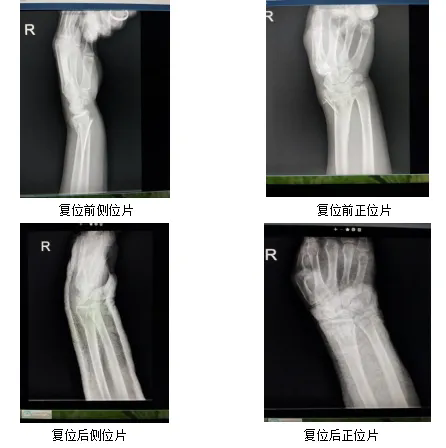

近日,一位宝鸡籍游人,在回民街游玩时不慎摔伤致右腕部肿胀、疼痛伴活动受限,遂被家人急送至省中医医院。骨伤一科胡锋医师接诊后,询问病史后,给予完善右腕部X线检查。X线提示:右侧桡骨远端骨折。经过与患者及家属充分沟通后,给予行中医正骨疗法。通过拔伸牵引、屈腕、尺偏等手法复位后,给予石膏固定。复查X线,复位满意。患者及家属赞叹:正骨术真神奇!